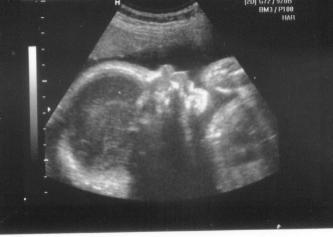

So, ehe ich es vergesse, will ich noch kurz von der VU gestern berichten, Wir hatten den Termin abends, weil die ganze Familie dabeisein wollte und es ja der dritte und damit letzte US war. Die Kinder waren sehr beeindruckt, fast mehr von den Herztönen als von den US Bildern. Mein Mann meint, vom Gesicht her würde er auf ein Mädchen tippen (mein Gefühl sagt aber eher Junge). Maße alle zeitgerecht, Gewicht geschätzt auf 1400g. Lage derzeit noch BEL, aber es hat ja noch genug Platz, um sich zu drehen, ich hab je erst Ende März ET. So, nun hoffe ich mal, dass man auf dem Bild was erkennt... LG Anne

Bild zu Gestern VU (mit Bild) - Forum für März - Mamis